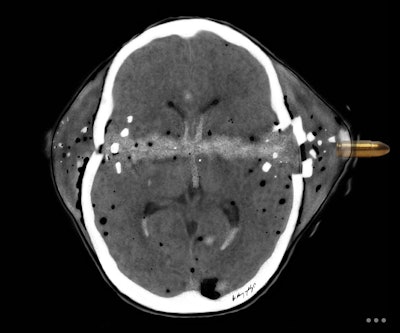

Conceptually, I think it is possible to define the term “radiological illustration” as an emerging discipline that transforms medical imaging data into an aesthetic and didactic narrative. I emphasize that with the motto “pixel by pixel handmade.” I am trying to open a “new path” for the use of visual communication in medical education by trying to combine scientific accuracy in radiological terms with artistic creativity. With this statement, I am trying to express that instead of modifying radiological images, I draw each pixel by hand using technological tools and create a new visual that is both artistically and scientifically original, while remaining faithful to radiological principles.